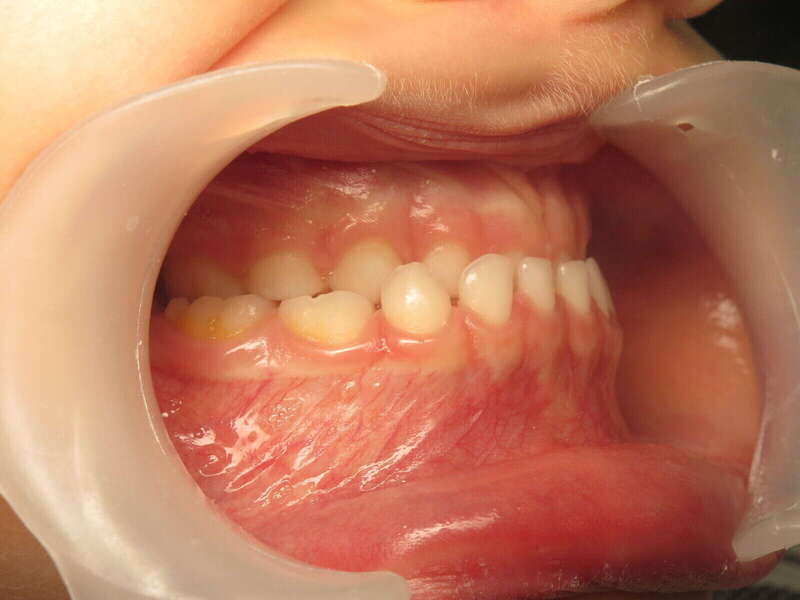

Cas n°1 traité par aligneurs (interception) - enfant

Ce cas d’interception chez un enfant de 8 ans démontre l'efficacité des aligneurs pour corriger des troubles fonctionnels précoces. Le diagnostic présentait des inversions d'articulé provoquant une déviation de la mandibule vers la gauche et un décalage des milieux.

Grâce à une coopération exemplaire et un traitement totalement indolore, l'expansion de l'arcade a permis de recentrer la mâchoire. Cette intervention a littéralement remis la croissance sur les rails, neutralisant le risque d'asymétrie faciale squelettique.

• Correction fonctionnelle : Recentrage immédiat de la mandibule et des milieux inter-incisifs.

• Prévention : Création d'un environnement favorable pour les dents définitives à venir.

• Bien-être : Approche douce respectant le confort de l'enfant.

C'est une étape fondamentale qui simplifie l'avenir orthodontique du patient tout en garantissant un développement facial harmonieux.